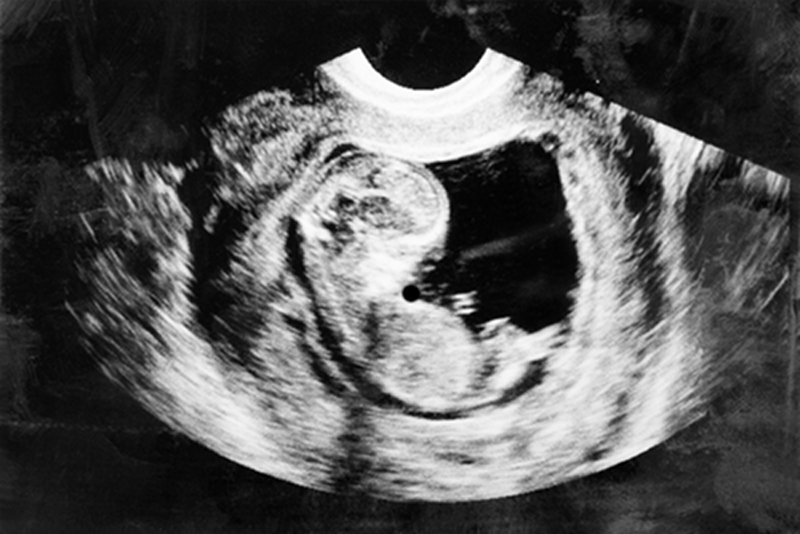

W komentarzach do tekstu opowiadaliście nie tylko o sobie. Wiele historii dotyczyło także znajomych, które poroniły. Nic dziwnego. W 2005 roku (ostatnie dane Ministerstwa Zdrowia) w Polsce miało miejsce 40 tys. poronień na 364,4 tys. żywych urodzeń. Z problemem musi zmierzyć się statystycznie jedna na dziesięć matek. Statystycznie więc w Waszym gronie znajomych musi być ktoś, kto poronił.